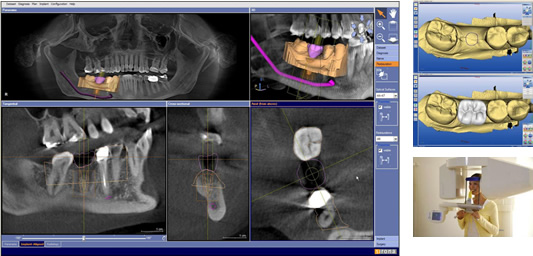

CAD/CAMシステム「セレック」と歯科用CT「ガリレオス」を用いたCEREC meets GALILEOS(インプラント治療診断・計画システム)により治療計画を立案します。

CEREC meets GALILEOS の良いところは、手術前から理想的な手術後の完成形がイメージしのインプラント治療ができることにあります。